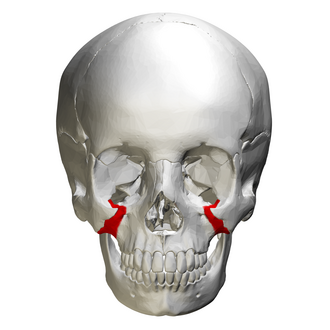

infraorbital foramen

hole in bone inferior to border or orbit

round radiolucency inferior to orbit, not seen intraoral